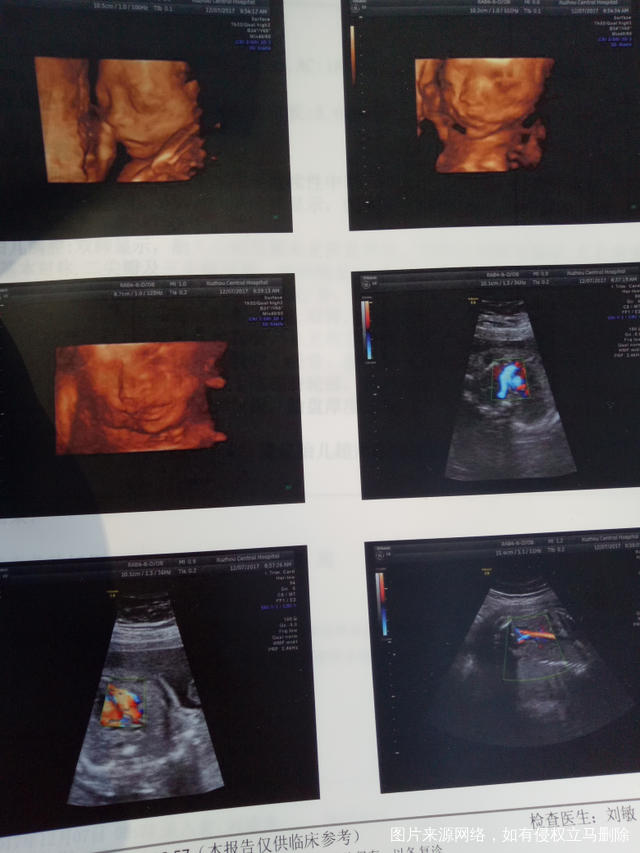

麻烦医生给看下四维结果